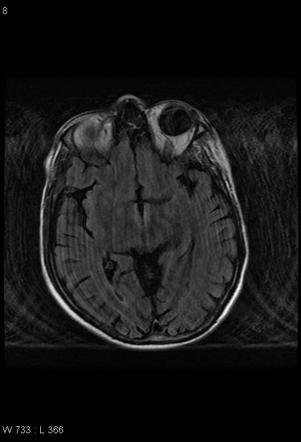

Uncal shift

vs

Uncal herniation

A

• uncal shift - just shifted out

• uncal herniation - bad - on coronal images, the uncus is on the other side of the tentorium! - blown pupil due to compression on the cisternal portion of the CNIII

• death occurs when there is mass effect on the adjacent midbrain